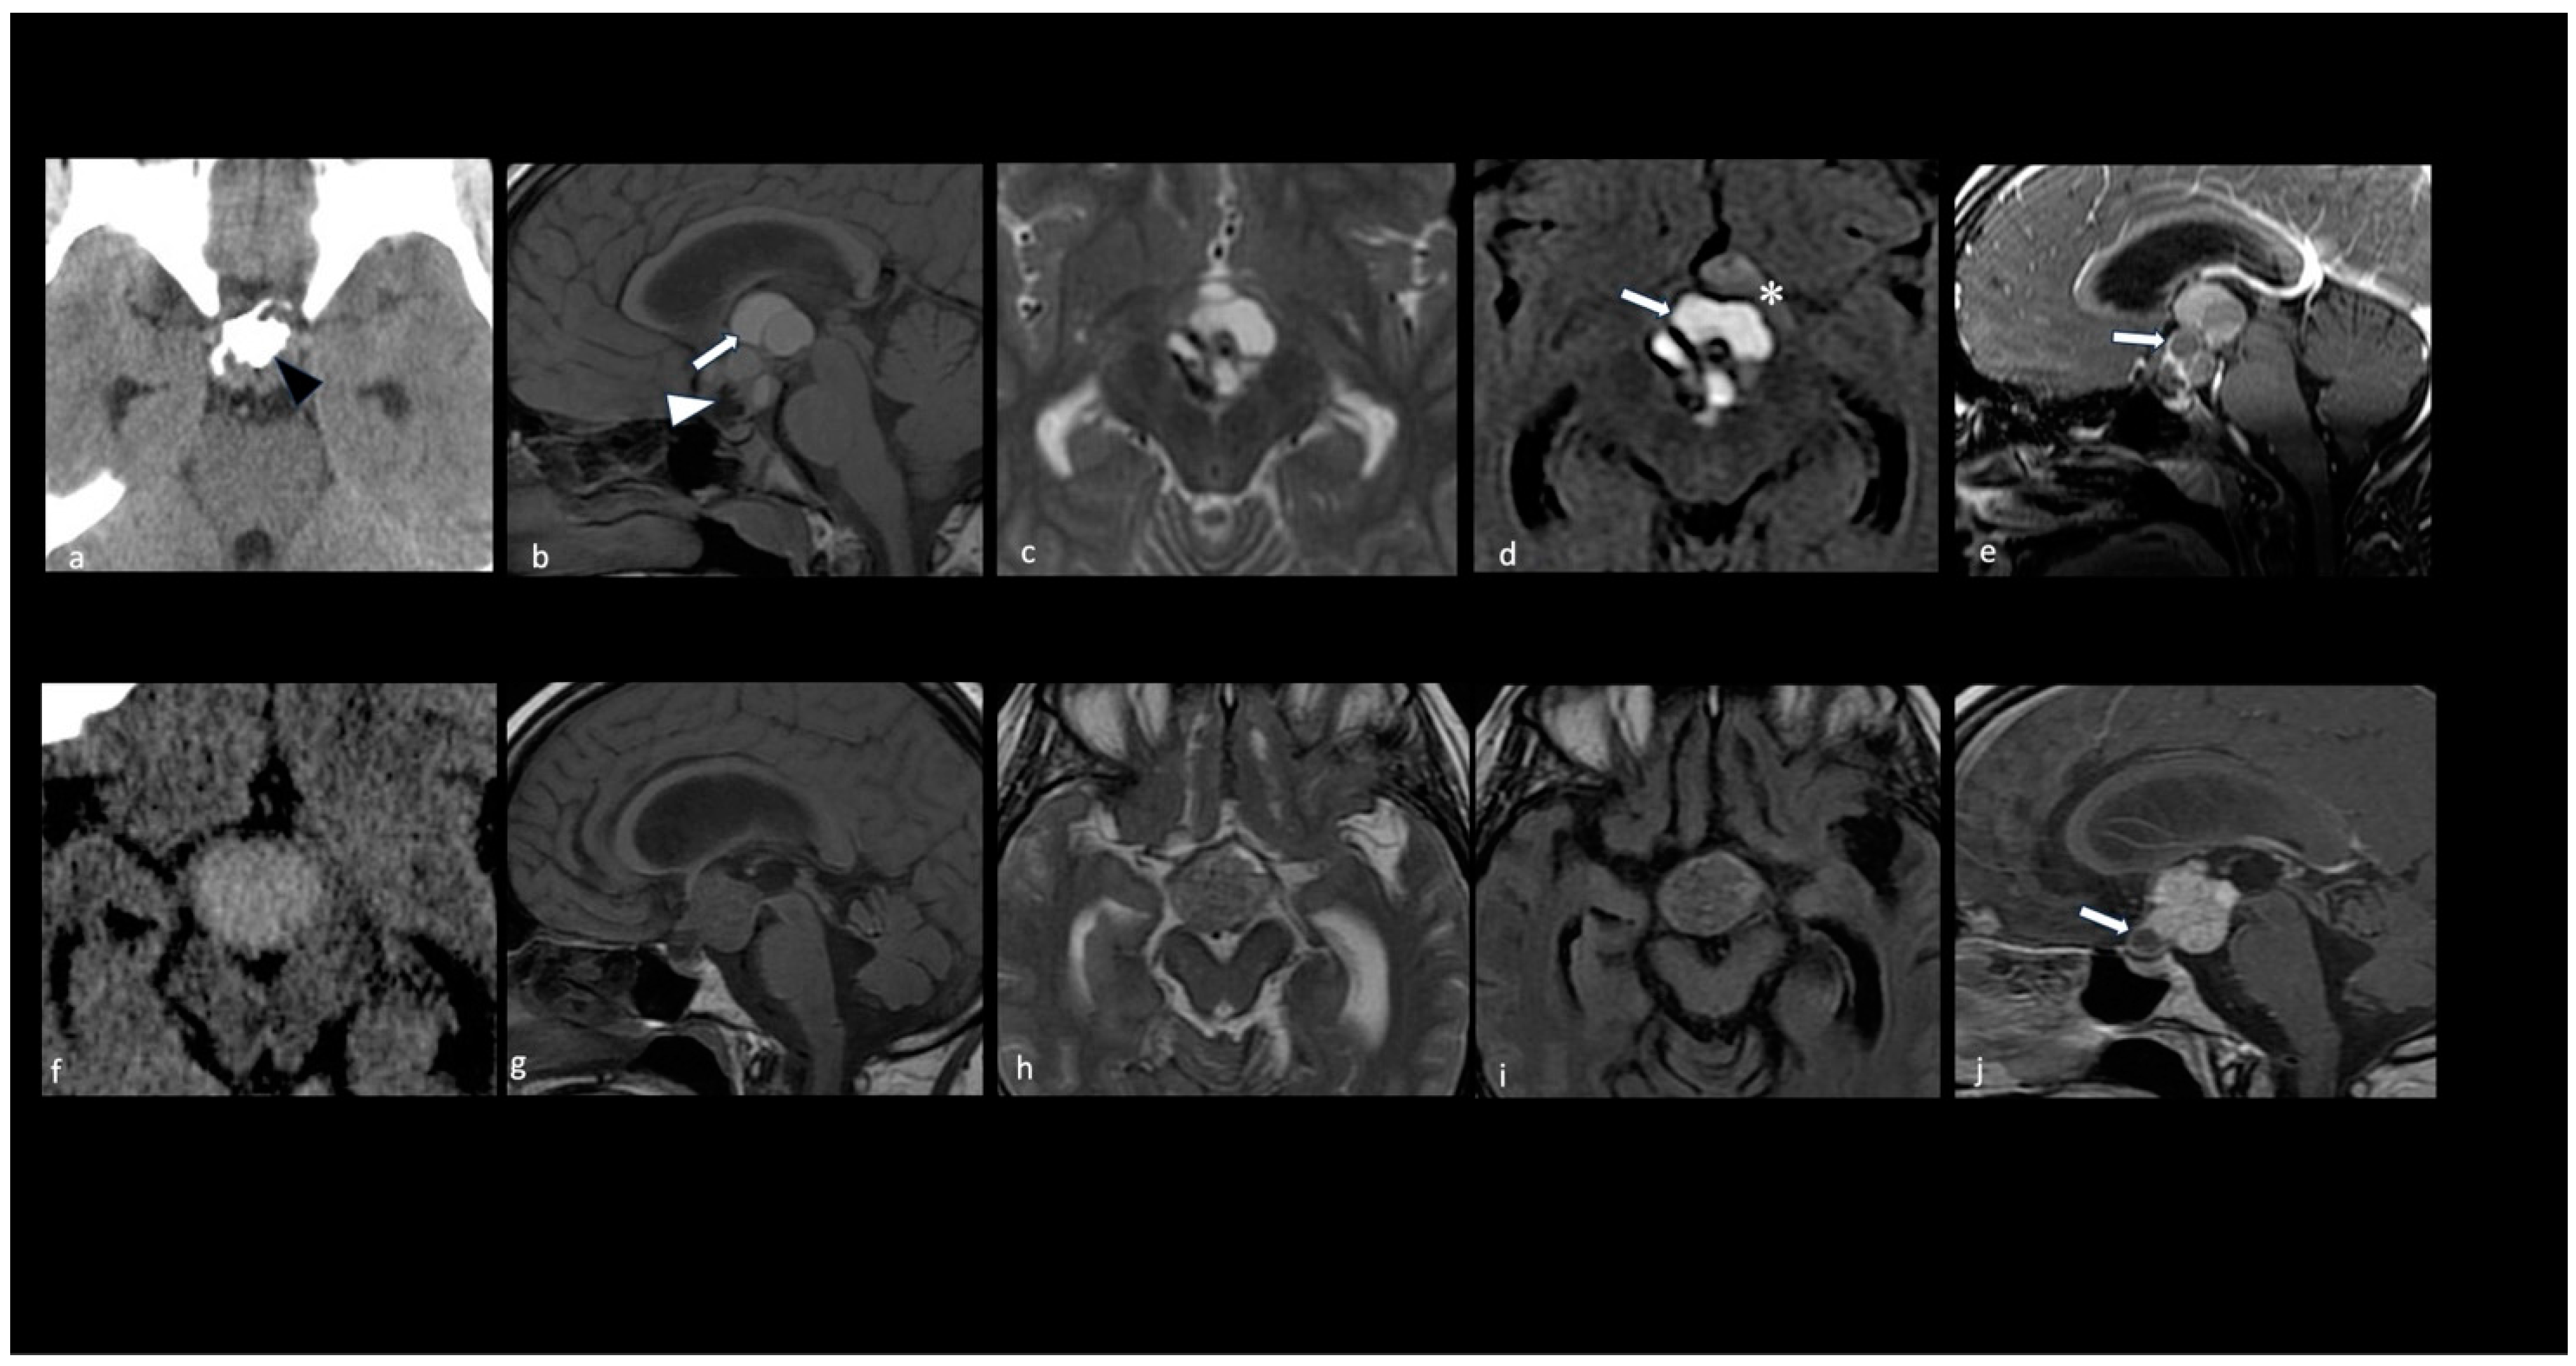

- Calandrelli, R.; Pilato, F.; Massimi, L.; D’Apolito, G.; Grimaldi, A.; Chiloiro, S.; Bianchi, A.; Gessi, M.; Gaudino, S. Pediatric Craniopharyngiomas: Magnetic Resonance Imaging Assessment for Hypothalamus-Pituitary Axis Dysfunction and Outcome Prediction. Pediatr. Radiol. 2024, 54, 157–169. [Google Scholar] [CrossRef]

- Prieto, R.; Pascual, J.M.; Rosdolsky, M.; Barrios, L. Preoperative Assessment of Craniopharyngioma Adherence: Magnetic Resonance Imaging Findings Correlated with the Severity of Tumor Attachment to the Hypothalamus. World Neurosurg. 2018, 110, e404–e426. [Google Scholar] [CrossRef] [PubMed]

- Hayashi, Y.; Sasagawa, Y.; Oishi, M.; Misaki, K.; Kozaka, K.; Tachibana, O.; Nakada, M. Radiological and Endocrinological Evaluations with Grading of Hypothalamic Perifocal Edema Caused by Craniopharyngiomas. Pituitary 2019, 22, 146–155. [Google Scholar] [CrossRef]